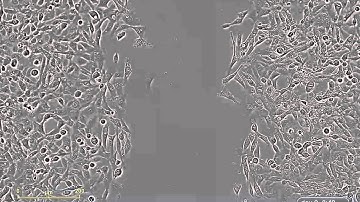

HSP90 Inhibitor